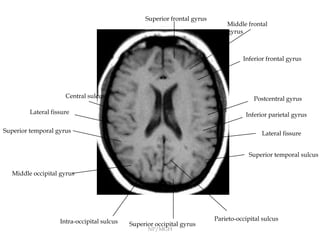

Surface Anatomy of the Brain | Radiology Key

Identification of Sulci and Gyri | Neuroanatomy | The Neurosurgical Atlas

Brain sulci and gyri: A practical anatomical review - ScienceDirect

The cerebral sulci and gyri in: Neurosurgical Focus Volume 28 Issue 2 (2010) Journals

The cerebral sulci and gyri